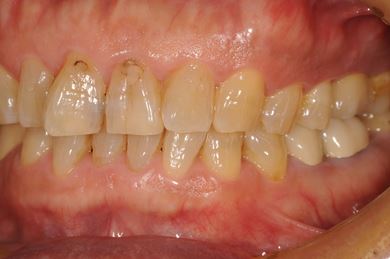

インプラントの症例写真 IMPLANT

インプラント治療+セラミック治療

| 主訴 | 部分入れ歯のバーが舌に当たるため、奥歯2本のインプラント治療を希望。 | ||||||||||||||||||||||||||||||||

| 治療方針 | 右下欠損部分をインプラント治療にて、機能的・審美的回復を行う。 | ||||||||||||||||||||||||||||||||

| 治療内容 | インプラント2本、メタルボンドセラミッククラウン8本、メタルボンドセラミック用土台6本 | ||||||||||||||||||||||||||||||||